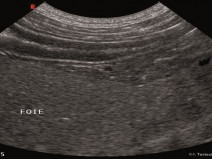

- décrire la présentation clinique des principaux cancers rencontrés dans l’espèce féline et les outils (biologiques, imagerie) indispensables de la démarche diagnostique ;